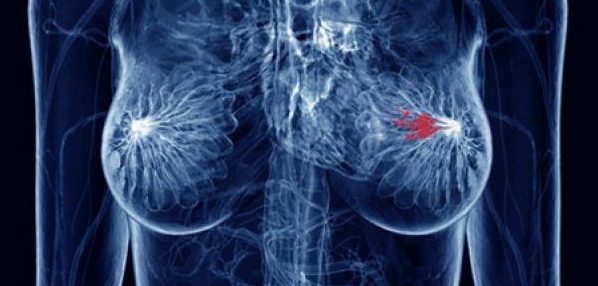

Tödlich für Frauen

In den USA werden jedes Jahr mehr Frauen mit Brustkrebs als Lungenkrebs diagnostiziert. So sollten die Todesfälle von Brustkrebs mehr als Lungenkrebs sein, aber das ist nicht. "Das ist, weil Brustkrebs oft in früheren Stadien gefangen ist als Lungenkrebs, und ein größerer Anteil an Brustkrebserkrankungen ist heilbar, sagt Antonoff.